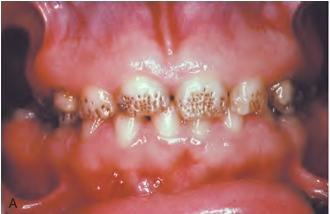

Xerostomia (dry mouth,口乾症) | - | 舌乳頭萎縮、鵝口瘡(oral candidiasis), 蛀牙 ![]() |